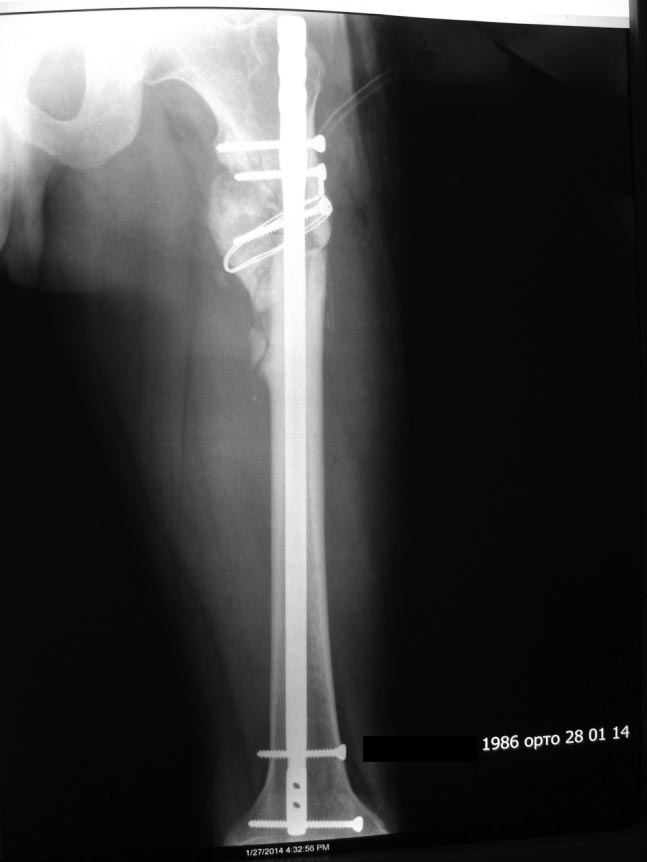

[Ortho] Предел одномоментного удлинения диафиза бедра?

Уважаемые коллеги! Предоставляем один свежих случаев, если что то не так

просим строго не судить!

С уважением Ерсин Жунусов